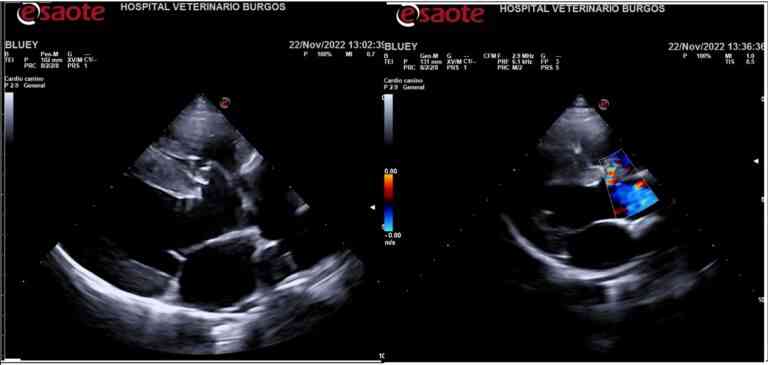

Recientemente, AniCura Burgos Clínica Veterinaria ha diagnosticado y tratado con éxito un importante caso de tetralogía de Fallot. Bluey, una perra de Braco de Weimar con 11 meses de edad, ha sido referida a este centro después de que su veterinario, al auscultarla, sospechara de un soplo cardiaco por un sonido similar a un silbido o susurro, producido por un flujo turbulento y anormal de la sangre en el corazón.

Para poder realizar un diagnóstico acertado y conocer la patología que afectaba a Bluey, fueron realizadas varias radiografías, un electrocardiograma y una ecocardiografía, que confirmaron que el animal padecía de tetralogía de Fallot. Este diagnóstico temprano fue posible gracias a la rápida acción de sus cuidadores, quienes siguieron las recomendaciones de su veterinario tras las revisiones y controles previamente realizados.